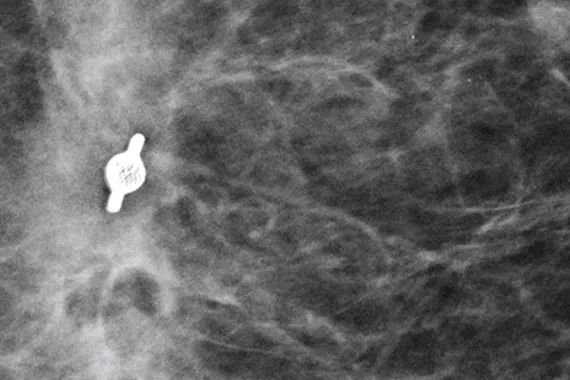

Intelligently designed to provide long-term visibility. All Tumark Markers are non-bioabsorbable, biocompatible permanent markers offering excellent visibility and are designed to minimise movement.1

Designed to minimise movement,2 this marker is highly visible in ultrasound upon deployment and still highly visible at 6 weeks post-biopsy, crucial in case of future breast interventions.3 The marker consists of two pieces, a permanent marker and a bioabsorbable suture-like netting.

Image Gallery